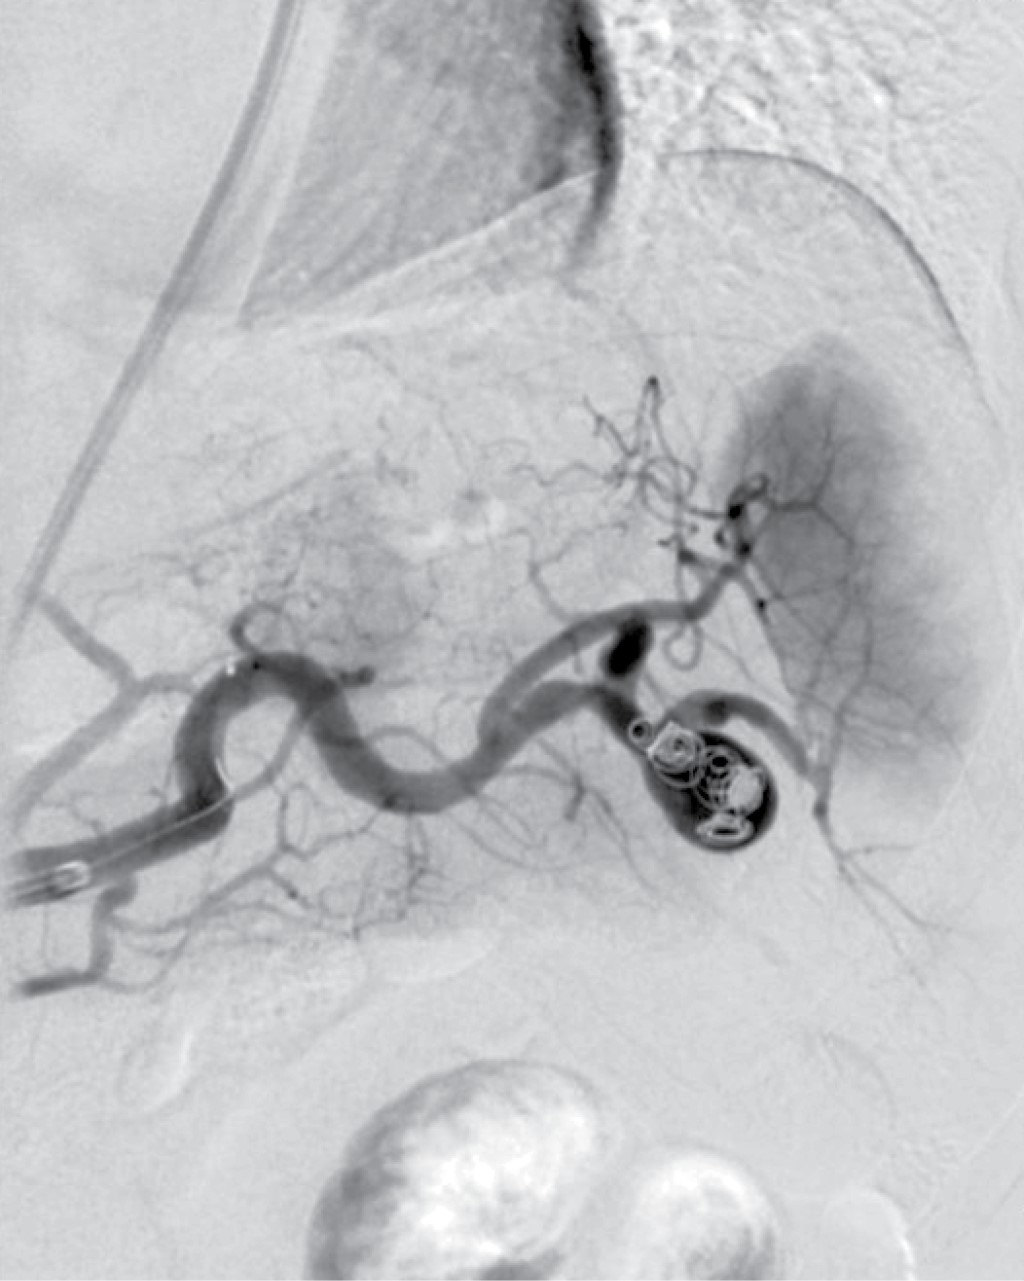

This was a 41-years old female patient with a history of hypothyroidism diagnosed at 21 years old, currently without medical treatment for 40 years old due to apparent control, diagnosis of uterine myomatosis at 40 years old, without treatment; history of two cesarean sections, being the last one at 23 years old, without complications. She suffered a car accident with rollover at age 40, without apparent organic damage. She began her current condition after a car accident one year earlier with intermittent, stabbing, non-radiating pain in the left hypochondrium, with no aggravating or extenuating factors; on physical examination, she presented pain in the left hypochondrium on deep palpation, with no other pathological findings. Ultrasound was performed with results compatible with an aneurysm of the splenic artery and cholelithiasis; the diagnostic approach was complemented with angio-tomography of the abdominal aorta finding a splenic artery of standard caliber, with focal saccular dilatation in distal segment compatible with an aneurysm of 17.7 × 15.9 mm and neck of 5.5 mm, with mural thrombus of 2 mm, with no signs of rupture; vesicular lithiasis and uterine myomatosis were also seen. With no apparent complications, selective embolization with coil placement was performed in conjunction with angiology (Figure 1). In the immediate follow-up, the patient presented abdominal pain and leukocytosis; a new angio-tomography was performed with data suggestive of splenic artery occlusion and splenic infarction (Figure 2). Due to the findings mentioned above, it was decided to perform splenectomy and conventional cholecystectomy using a surgical approach with a midline supraumbilical incision, with the following findings: Thin-walled gallbladder, multiple calculi inside of 5-10 mm approximately, cystic artery of 2 mm, cystic duct of 3 mm, spleen of 13 × 10 cm approximately, with multiple ischemic areas, an aneurysm of the splenic artery at the level of the splenic hilum, posterior to its bifurcation (Figure 3). The postoperative course was without complications, so she was discharged three days after surgery and received the corresponding vaccination for patients with splenectomy. The histopathological report included findings of splenic artery aneurysm with atherosclerosis, splenic parenchyma with congestive vessels, and chronic calculous cholecystitis.

Endovascular treatment is indicated in high-risk cases, hostile abdomen, and distal lesions. Some options are splenic artery embolization with coils and functional exclusion, placement of a stent covering the neck of the aneurysm, and embolization with locks for hilar aneurysm with spleen preservation. The advantages are minimal invasion, rapid recovery, and preservation of the flow to the spleen, but it requires radiation and the use of contrast. Another alternative is the injection of fibrin glue into the aneurysmal sac. It is essential to consider whether to preserve the spleen since splenic infarction predisposes patients to infection.8 Theoretically, a combination of stenting and coil embolization is more appropriate for these aneurysms than other endovascular methods. Embolization is considered the first line of treatment in asymptomatic aneurysms, in patients difficult to manage surgically or in pseudoaneurysms. It is contraindicated in cases of aneurysms of the splenic hilum or in instances of tortuosity of the artery, in which open surgery is preferred. The objective of an embolization is the occlusion of blood vessels using numerous embolic agents, each with different properties and uses. This is the basis of mechanical obstruction, platelet activation, and activation of the patient's coagulation cascade to obstruct the vessels completely. Coils are among the most widely used embolic agents, varying in diameter from submillimeter to several centimeters; their shape is also very variable (straight, helical, spiral, and three-dimensional), and they also have a thrombogenic coating; they are placed using a guide catheter that accesses the aneurysm. Most coils have small fibers attached to the metal component, which provoke a thrombogenic response with subsequent vessel occlusion. Different series report a 66.7 to 92% success rate with this technique. However, patients should be observed after surgery for possible complications such as infarction due to coil migration, splenic abscess, aneurysm rupture, pancreatitis, and rarely recanalization.10,13,14 Coil embolization of the splenic artery can cause a splenic infarction, mainly after distal embolization or in the splenic hilum, with a reported incidence of 25%. Symptoms vary from abdominal pain and low-grade fever to sepsis, pancreatitis, infection, or abscesses of the splenic parenchyma.14 Open surgery was the gold standard of treatment until the end of the 20th century and is generally indicated in low-risk patients for trunk lesions or when aneurysms are also present in the aorta or intestinal arteries and in patients in whom endovascular treatment has failed. Conventional surgery consists of raffia of the aneurysm, double ligation of the splenic artery with or without splenectomy, aneurysmectomy with arterial reimplantation, or grafts that can also be performed.8 In the proximal third, aneurysmectomy will be performed; in the middle third aneurysmal exclusion is preferred, as well as splenoaneurysmectomy if it is in the distal third.2,10

Figure 1